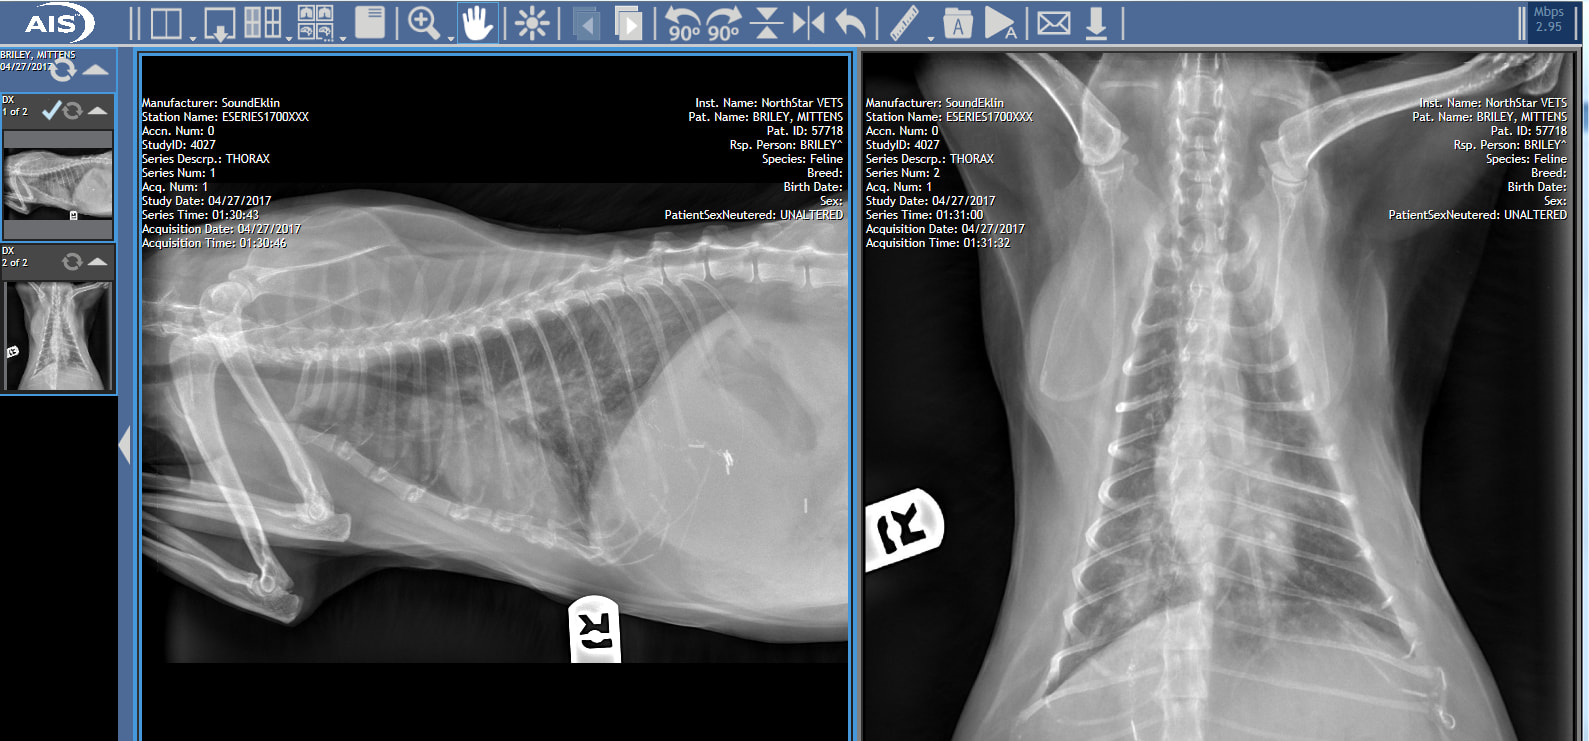

My cat is 16 y/o, spayed female. Past hx of cystadenoma with liver lobectomy, chole, 2 years ago. 6 weeks ago, she had a mild cough, dvm was not concerned. It progressed, she was diagnosed pneumonia, no improvement with antibiotics. She's on oxygen now. RR 80 on 40% O2, slight effort. Vets can not diagnose as they are not sure it is pneumonia d/t progression of x-rays over 2 weeks, also not consistent with cancer.

I'm sorry to hear that Mittens has not been doing well. I agree that Mittens' chest x-rays appear to be progressing over the past 2 weeks. At this point, either pneumonia is less likely or the bacteria causing a possible pneumonia are resistant to her current antibiotic therapy. Cancer is absolutely a suspicion due to the x-ray progression. Consider asking your vets if they have considered performing either endotracheal or transtracheal washes on Mittens, which would be able to obtain a sample of fluid or cells in the lungs. These samples could be analyzed for cytology (which may be able to diagnose cancer) or culture (to determine if bacteria is present and an appropriate antibiotic). There is a chance that Mittens may not be stable enough to undergo sedation for this procedure, but your vets will be able to examine her to determine if the risks are worth the benefits. I hope that all goes well!